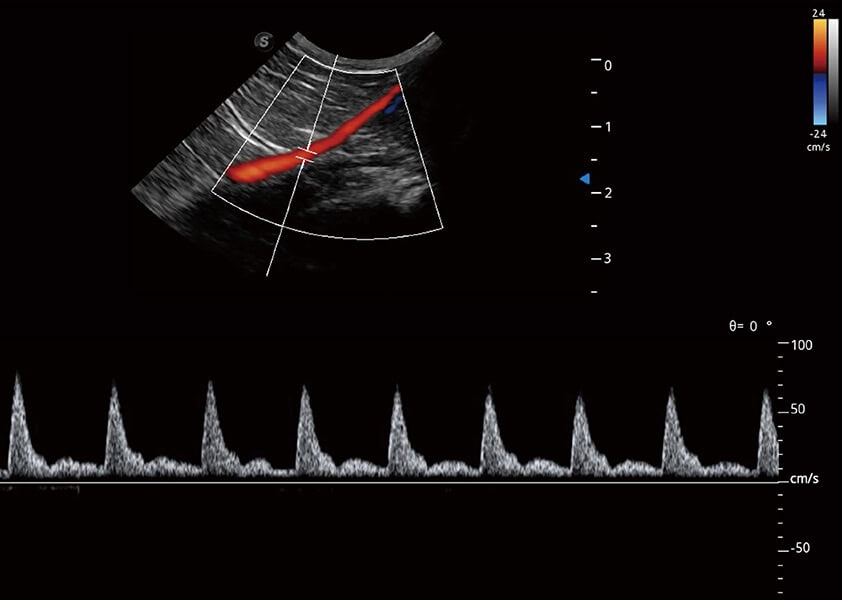

优异的基础图像

(猫)髂动脉血流频谱

(犬)肾脏血流